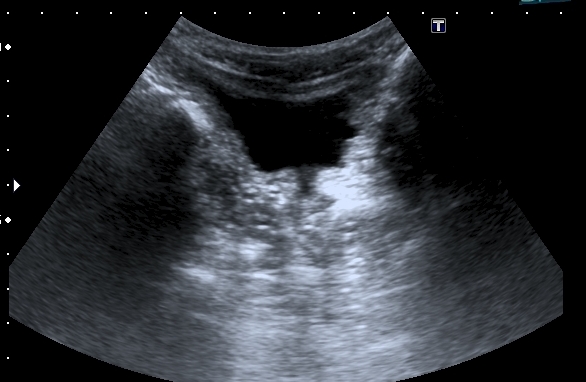

Почки:

Определяется небольшое расширение лоханок обеих почек, стенки их гиперэхогенные, утолщены.

Меня больше всего заинтересовало тканевое образование в нижнем полюсе левой почки - гиперэхогенное, многоузловое. Есть мысли про причину такого состояния почек, но пока хочу выслушать мнения коллег. Буду очень благодарен за отзывы.

"Маленькие белые почки" с расширением ЧЛС и мочеточников, умеренной латерализацией устьев, без видимых на высокочастотном УЗИ кист. Печень без видимых на высокочастотном УЗИ кист. Опухоль слева.

Сергей Васильевич, большое спасибо. Посмотрел ребёнка ещё раз. Согласен с рефлюкс - нефропатией и опухолью. Единственное , что меня смущает - проксимальная уретра, не широковата ли она?. В простате - небольшие парауретральные обызыствления (?) - редкость для ребёнка.